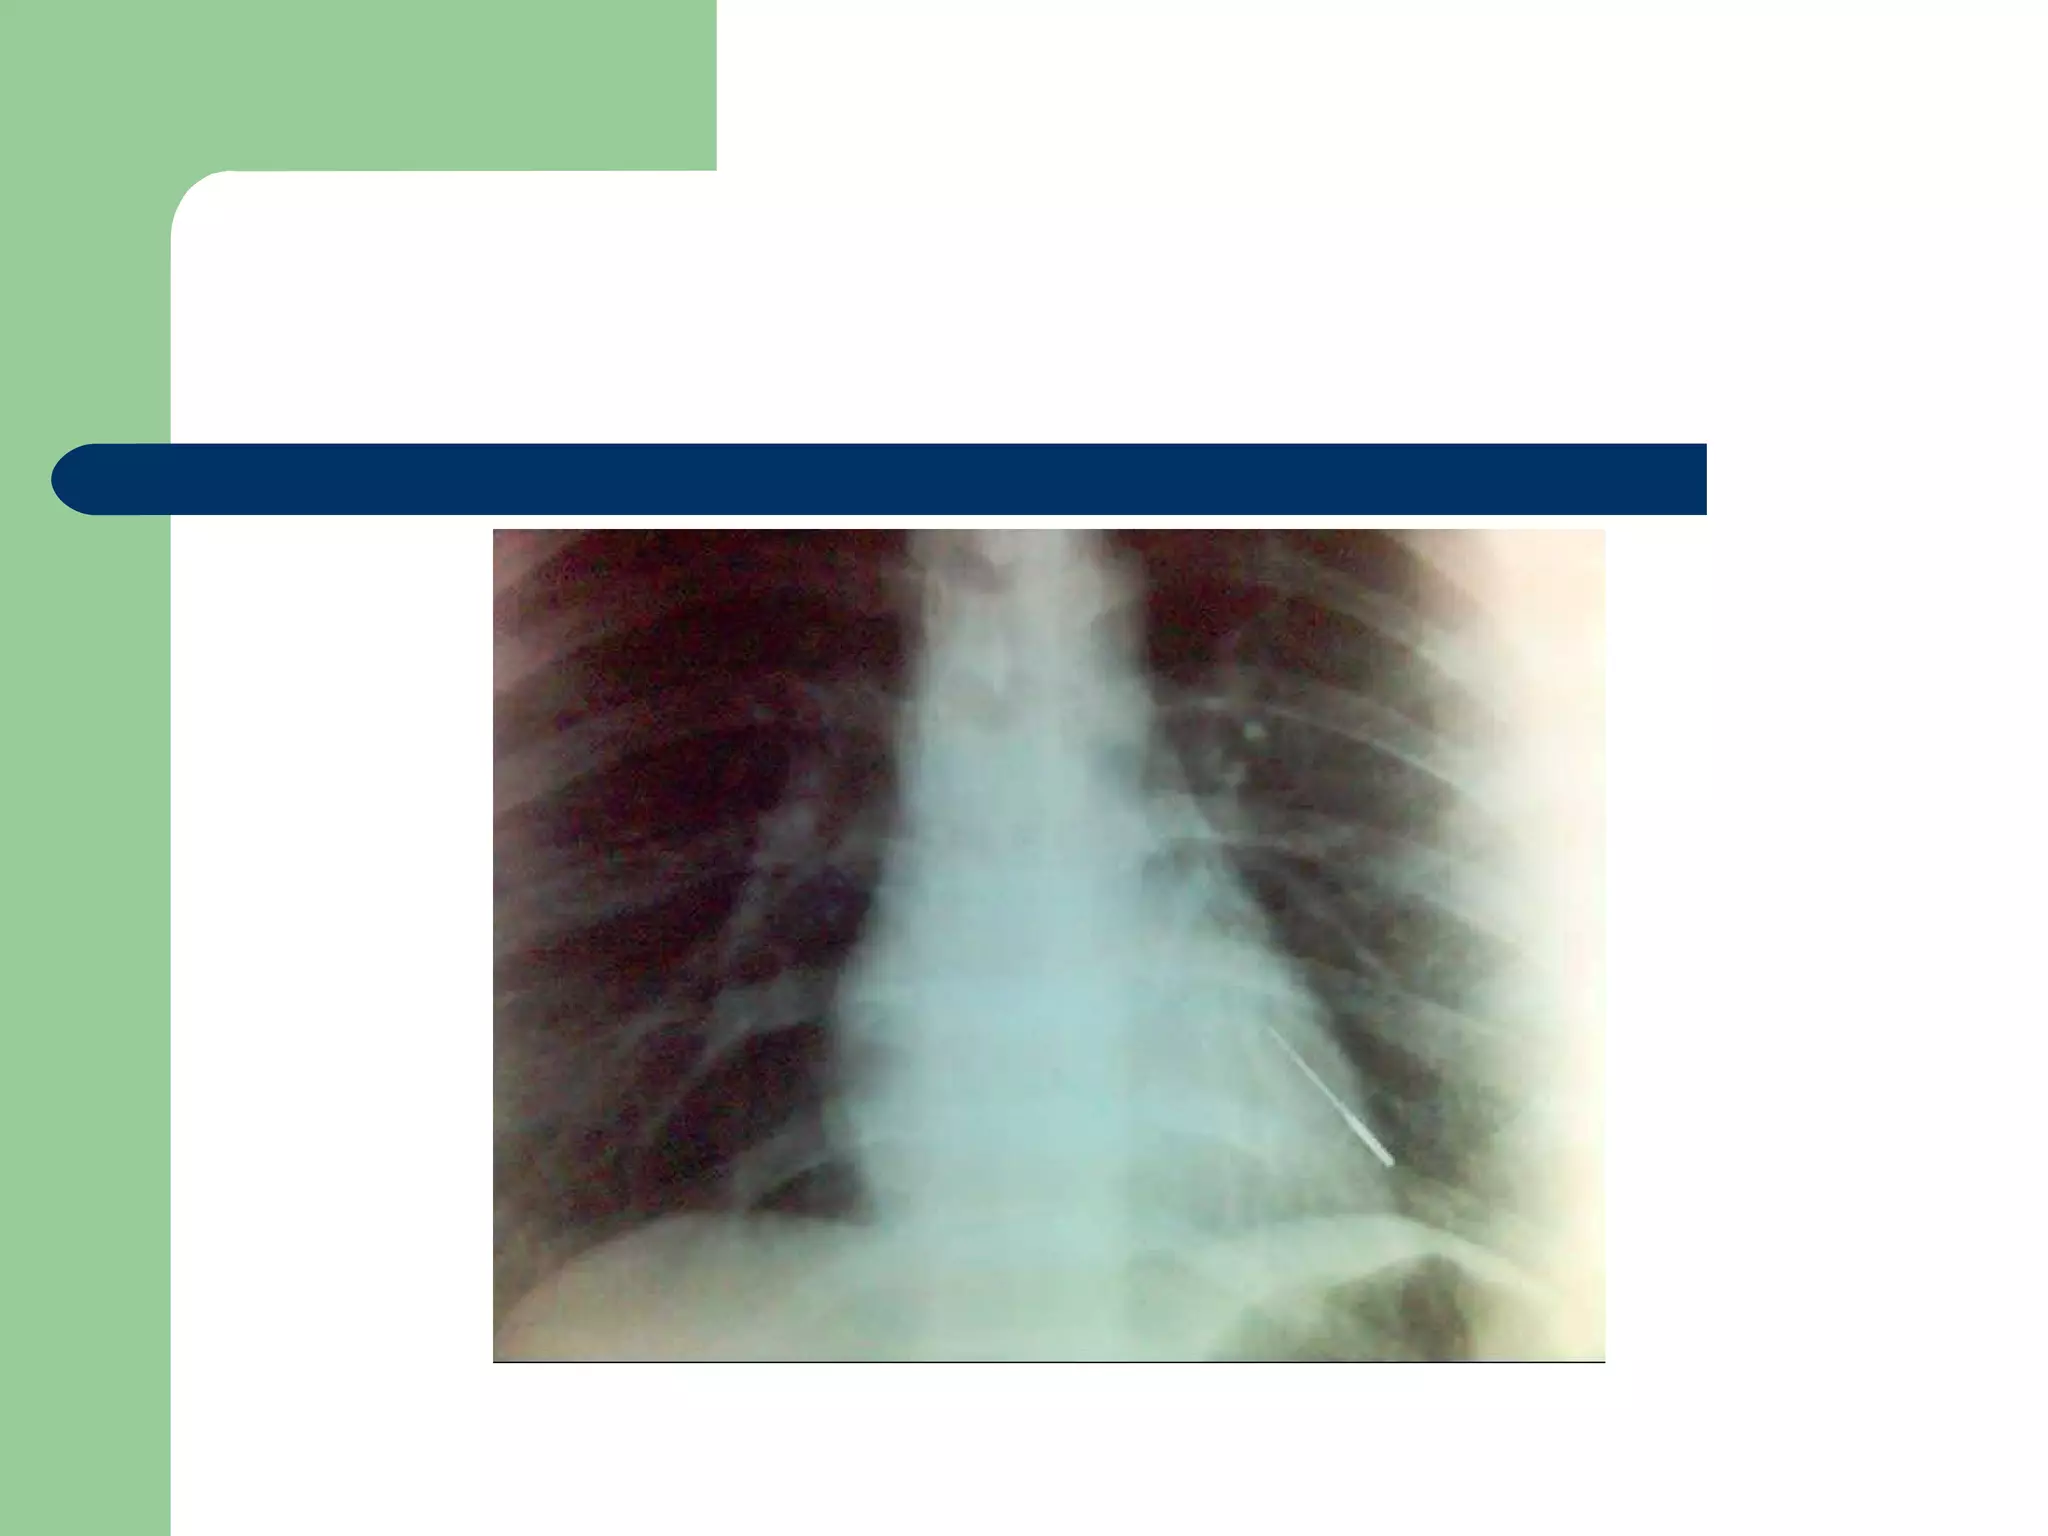

A five and a half yr old boy: non-resolved cough

Of 40 days duration

DIAGNOSIS…  Examination:signs of respiratory distress may be present.  CXR may be normal if the FB is not radio- opaque. or it can show a radio- opaque FB such as bone. Obstructive emphysema: is produced by intra-bronchial FB that allows air to enter in inspiration and prevents its exit in expiration. Lung collapse (complete or partial) is produced by a FB that blocks the bronchus completely. Unresolved pneumonic consolidation. Lung abscess or broncheictasis are caused by a long-standing FB.

A five anda half yr old boy: non-resolved cough Of 40 days duration